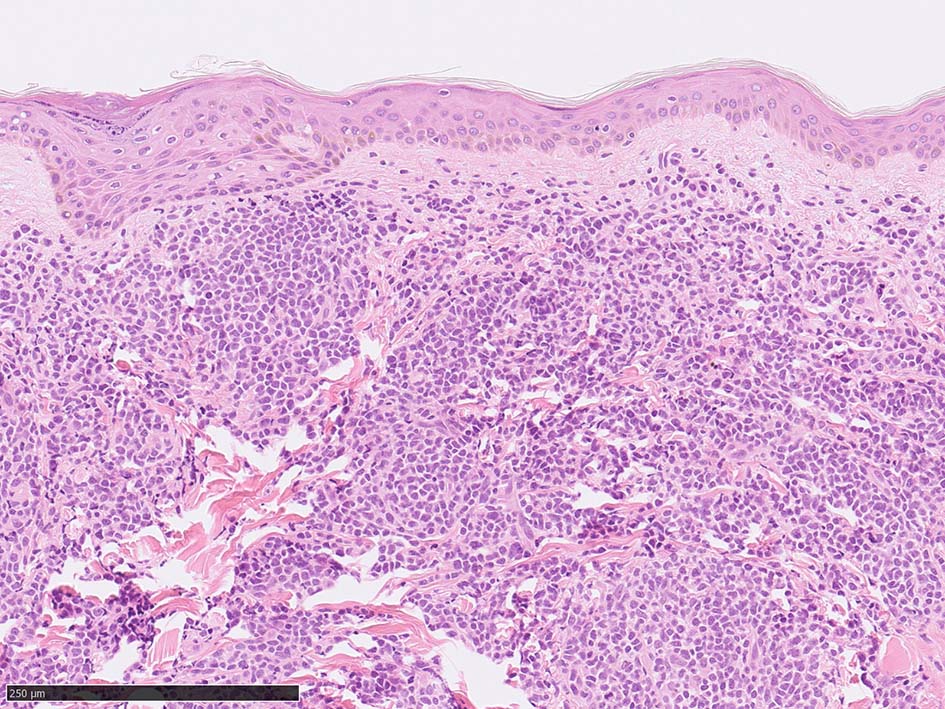

皮膚病変

IWT-case: 4つの点で囲んだ紅斑から生検.

皮膚病変は64-100%の症例で認められ皮膚病変が契機となり診断されることも多い.

マクロ所見は多彩で, 孤在性から播種性の分布を呈し, 腫瘤, 局面, 紅斑いずれの形態もとりえる.

腫瘍細胞は真皮を主座として, 皮下脂肪織まで, びまん性かつ単調monotonousに増殖することが多く, 表皮向性はみられない.